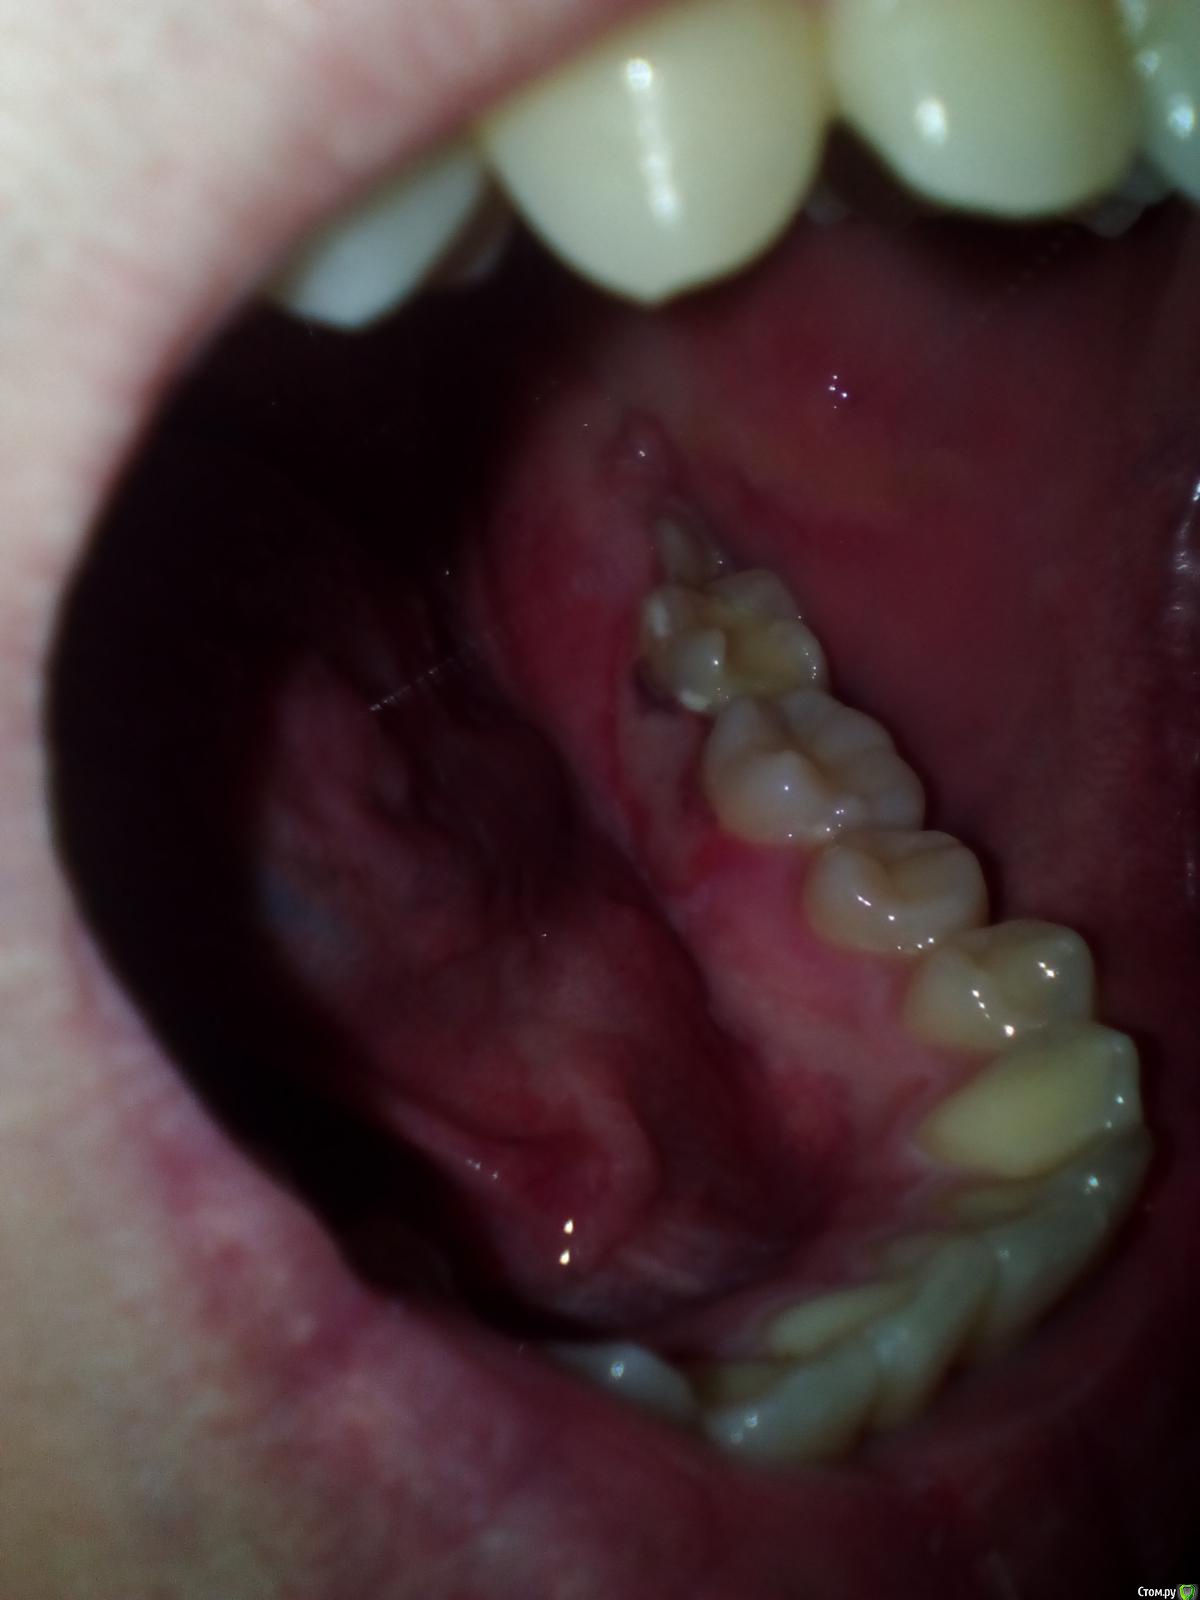

Reiegal Опубликовано 23 сентября, 2017 Поделиться Опубликовано 23 сентября, 2017 21 сентября лечили пульпит - очистили каналы, закрыли временной пломбой. На первый день десна около зуба опухла, на второй (сегодня) побелела. Звонил в стоматологию, по выходным она не работает, ближайший прием - в понедельник. Что это такое, обратимо ли это?http://s018.radikal.ru/i516/1709/bc/8ecad46f48d3.jpg Ссылка на комментарий

kramer Опубликовано 23 сентября, 2017 Поделиться Опубликовано 23 сентября, 2017 Заживет Ссылка на комментарий